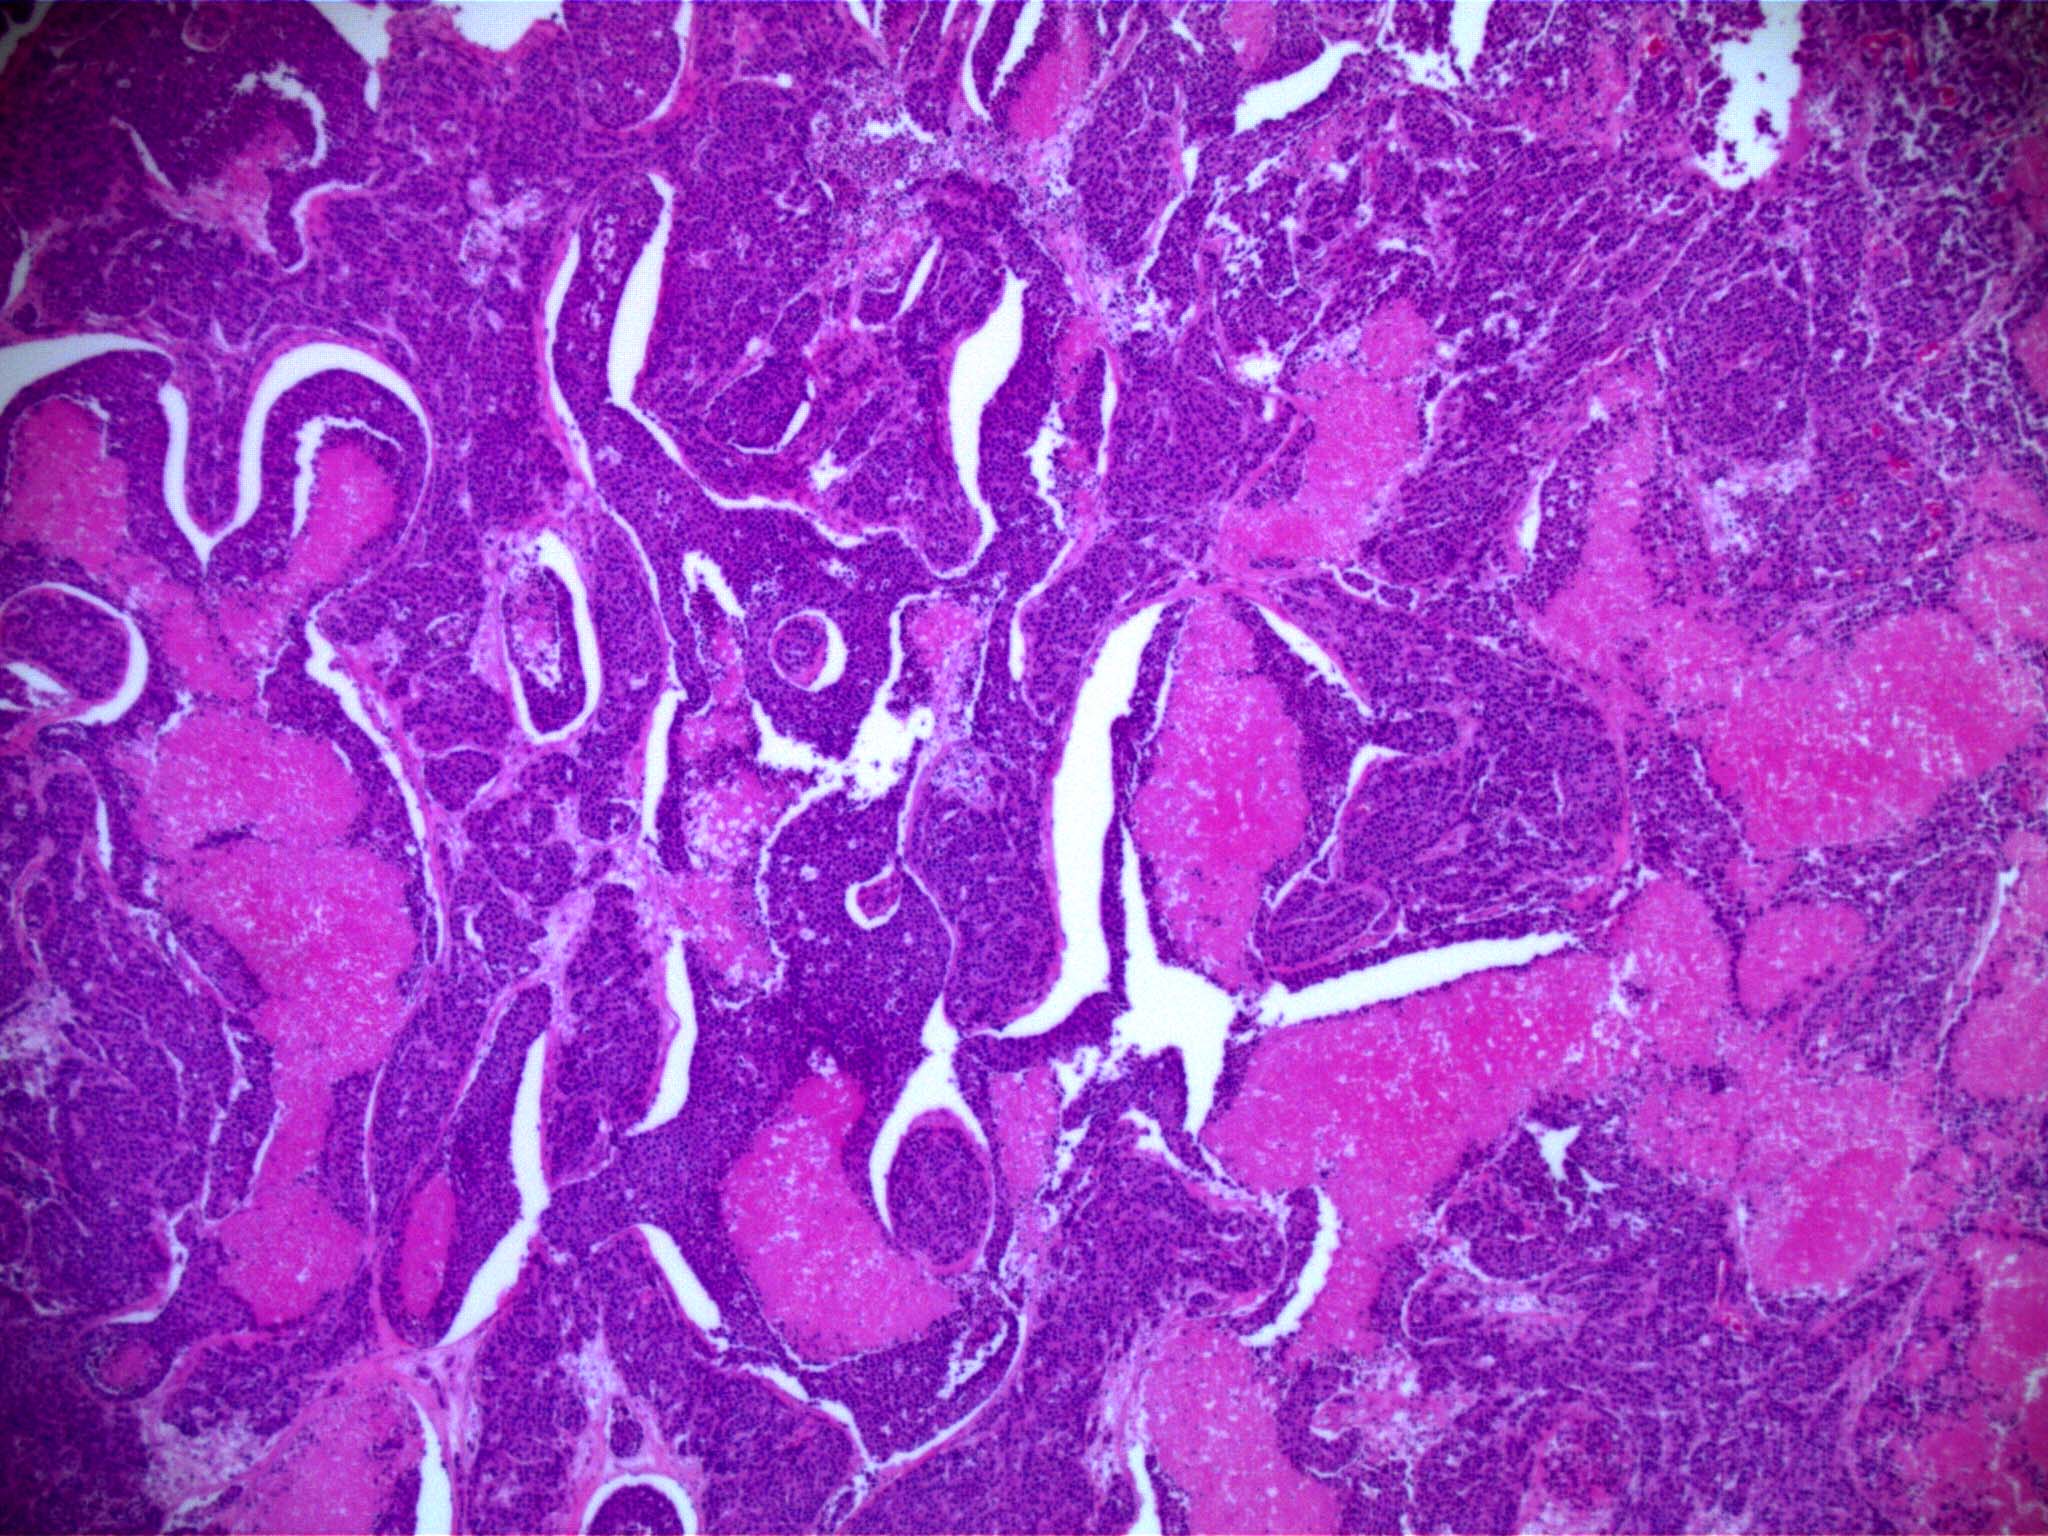

Munson Lab Vt . The munson lab studies the tumor microenvironment in cancers, including glioblastoma, the deadliest form of brain cancer. Our research program aims to understand and harness the tumor microenvironment to study and treat triple negative breast cancer and. Jenny munson is a principal investigator at the fralin biomedical research institute who studies the tumor. Our research focuses on the. Led by principal investigator jenny munson, ph.d., director of the fralin biomedical research institute cancer reearch group, the munson. Jennifer munson, associate professor at the fralin biomedical research institute at vtc, shared her data on fluid flow in brain tumors with virginia. In 2019, he started his postdoctoral research at ucsf in dr. Engineering cancer to cure it. Jennifer munson, associate professor at the fralin biomedical research institute at vtc, shared her data on fluid flow in. Our mission is to investigate and evaluate the tumor microenvironment, the tissue around a tumor that is involved in invasion and metastasis.